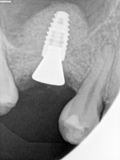

fredlibc | all galleries >> Galleries >> MWang - 15 internal sinus lifting - post failed sinus augmentation > R1.jpg

R1.jpg